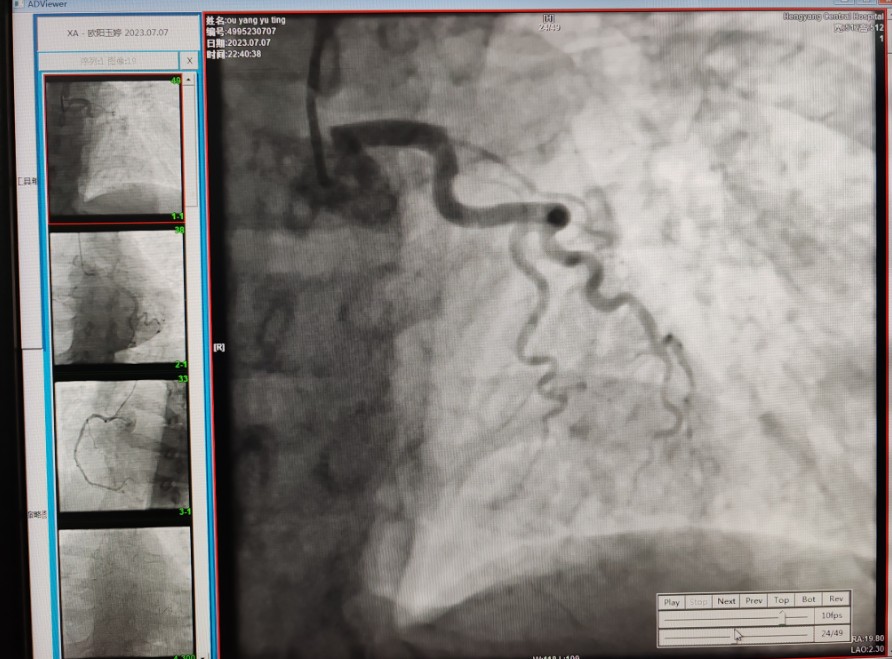

22:29分患者經(jīng)院內(nèi)綠色通道送達(dá)導(dǎo)管室,手術(shù)由雷剛副主任醫(yī)師主刀,楊繼賀副主任醫(yī)師為第一助手,介入技師及護(hù)士密切配合,聞?dòng)嵍鴣淼内w慶禧主任醫(yī)師坐鎮(zhèn)協(xié)調(diào)指揮。22:37分手術(shù)開始,冠脈造影顯示心臟上最重要的一條冠狀動(dòng)脈-前降支開口齊頭閉塞,血管粗大且血栓高負(fù)荷,非??简?yàn)介入術(shù)者的手術(shù)能力,一旦發(fā)生冠脈無(wú)復(fù)流或操作不慎血栓帶入回旋支導(dǎo)致循環(huán)崩潰,病人幾乎無(wú)生還希望;此時(shí),患者手術(shù)臺(tái)上仍持續(xù)胸痛,且血氧飽和度在高流量吸氧狀態(tài)下不到80%,雷剛副主任醫(yī)師一方面指揮鎮(zhèn)靜鎮(zhèn)痛及抗心衰治療,一方面緊急啟用IABP(主動(dòng)脈球囊反搏),然后精細(xì)操控細(xì)如發(fā)絲的介入導(dǎo)絲迅速通過病變,并予冠脈球囊擴(kuò)張、冠脈內(nèi)溶栓、抗痙攣藥物使用、植入冠脈支架,最終成功開通“罪犯”血管,且無(wú)手術(shù)并發(fā)癥發(fā)生,整個(gè)過程張弛有度、快慢結(jié)合、一氣呵成。患者術(shù)后胸痛明顯好轉(zhuǎn),血氧飽和度上升至96%,術(shù)后1天轉(zhuǎn)出監(jiān)護(hù)病房,第3天拔出IABP,目前已康復(fù)出院。